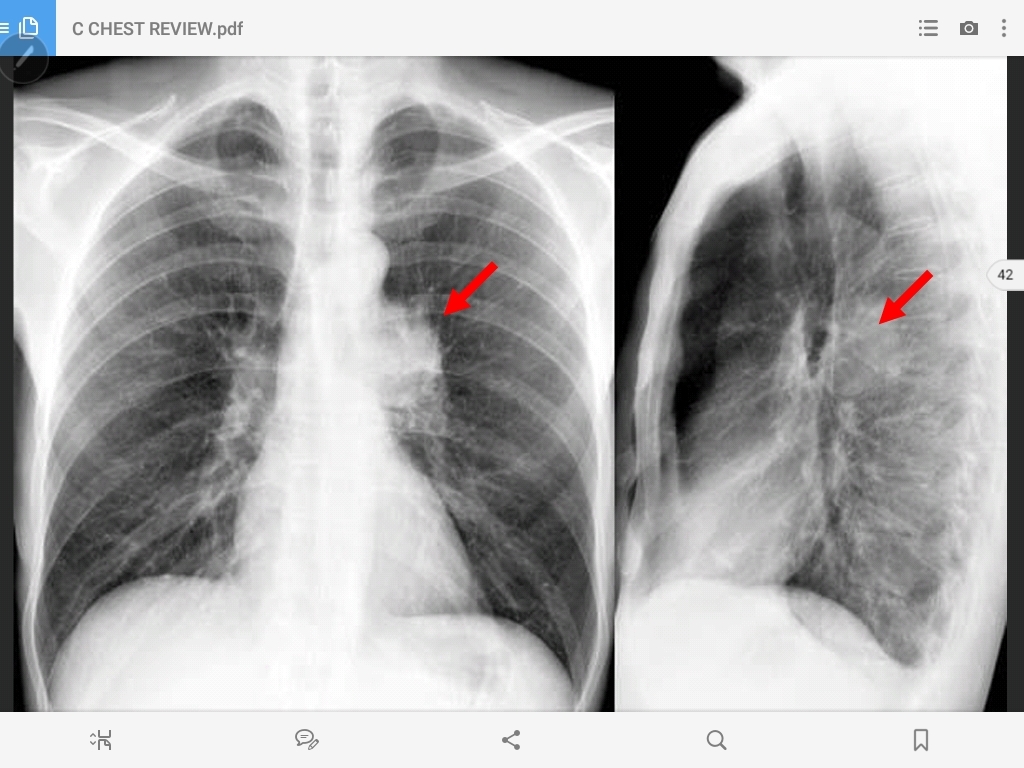

enlarged hilum (bronchogenic carincoma

enlarged hilum (bronchogenic carincoma)